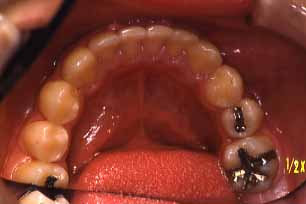

矯正後

上顎

(ミラー像)